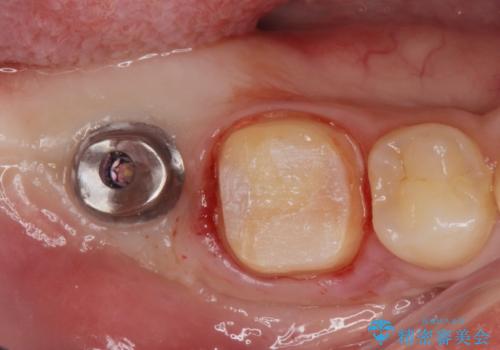

右下の被せ物を外し虫歯を除去したところ虫歯が深く保存が難しい状態だったので抜歯を行いました。

手前の銀の詰め物のところは除去して拡大鏡下で虫歯を取り除き、ジルコニアクラウンで治療を行いました。

抜歯したところは抜歯後骨の治癒を待ち、CTを撮影しインプラント治療ができる事(骨の厚みなど)確認し治療を行いました。

白くて綺麗な被せ物が入りました。